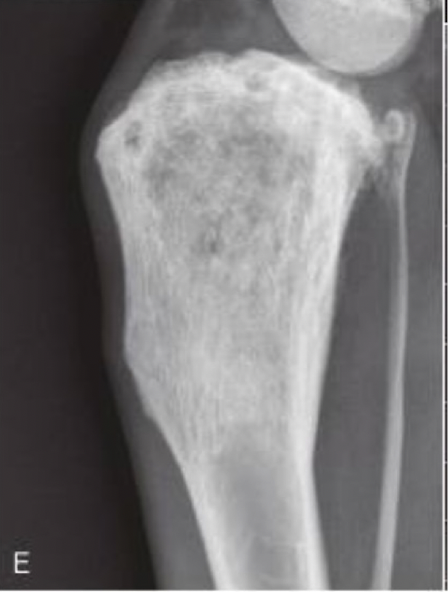

xray of OSA will show

A

cortical destruction

lysis- moth eaten or permeative

periosteal proliferation: codman’s triangle

medium to long zone of transition

rarely crosses joint